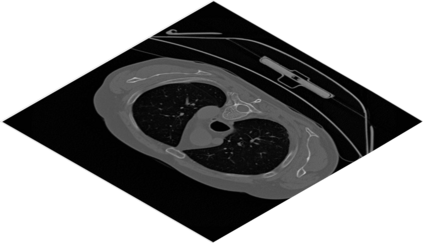

Deep Convolutional Neural Networks (DCNNs) are used extensively in biomedical image segmentation. However, current DCNNs usually use down sampling layers for increasing the receptive field and gaining abstract semantic information. These down sampling layers decrease the spatial dimension of feature maps, which can be detrimental to semantic image segmentation. Atrous convolution is an alternative for the down sampling layer. It increases the receptive field whilst maintains the spatial dimension of feature maps. In this paper, a method for effective atrous rate setting is proposed to achieve the largest and fully-covered receptive field with a minimum number of atrous convolutional layers. Furthermore, different atrous blocks, shortcut connections and normalization methods are explored to select the optimal network structure setting. These lead to a new and full-scale DCNN - Atrous Convolutional Neural Network (ACNN), which incorporates cascaded atrous II-blocks, residual learning and Fine Group Normalization (FGN). Application results of the proposed ACNN to Magnetic Resonance Imaging (MRI) and Computed Tomography (CT) image segmentation demonstrate that the proposed ACNN can achieve comparable segmentation Dice Similarity Coefficients (DSCs) to U-Net, optimized U-Net and hybrid network, but with significantly reduced trainable parameters due to the use of full-scale feature maps and therefore computationally is much more efficient for both the training and inference.